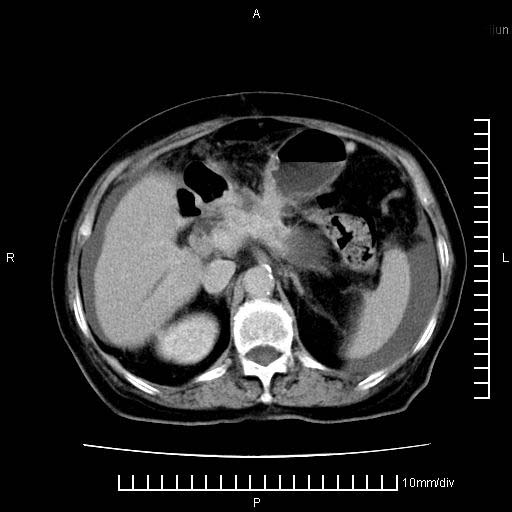

标题: CT28280:腹部增强:女性,80岁

上腹疼痛月余,外院核磁诊断胰腺癌。现临床示右下腹可明显触及包块,可片子上怎么没有看到?

1.胰腺颈体部癌。

胰腺体部癌累及周围器官,腹膜、粘连

胰腺体部癌累及周围器官,腹膜、粘连,临床摸到的可能是粘的组织

胰腺结构模糊,胰尾部见囊性包块,周围脂肪密度增高,左肾前筋膜增厚,胸水、腹水。不符合胰腺ca伴腹膜腔转移。考虑胰腺炎伴假性囊肿形成、胸腹腔积液。

1)考虑胰腺癌并胰腺假性囊肿形成。2)肝内低密度灶,不排除转移。3)右肾盂积水。4)腹水。5)右侧胸腔积液并右肺下叶部分膨胀不全。